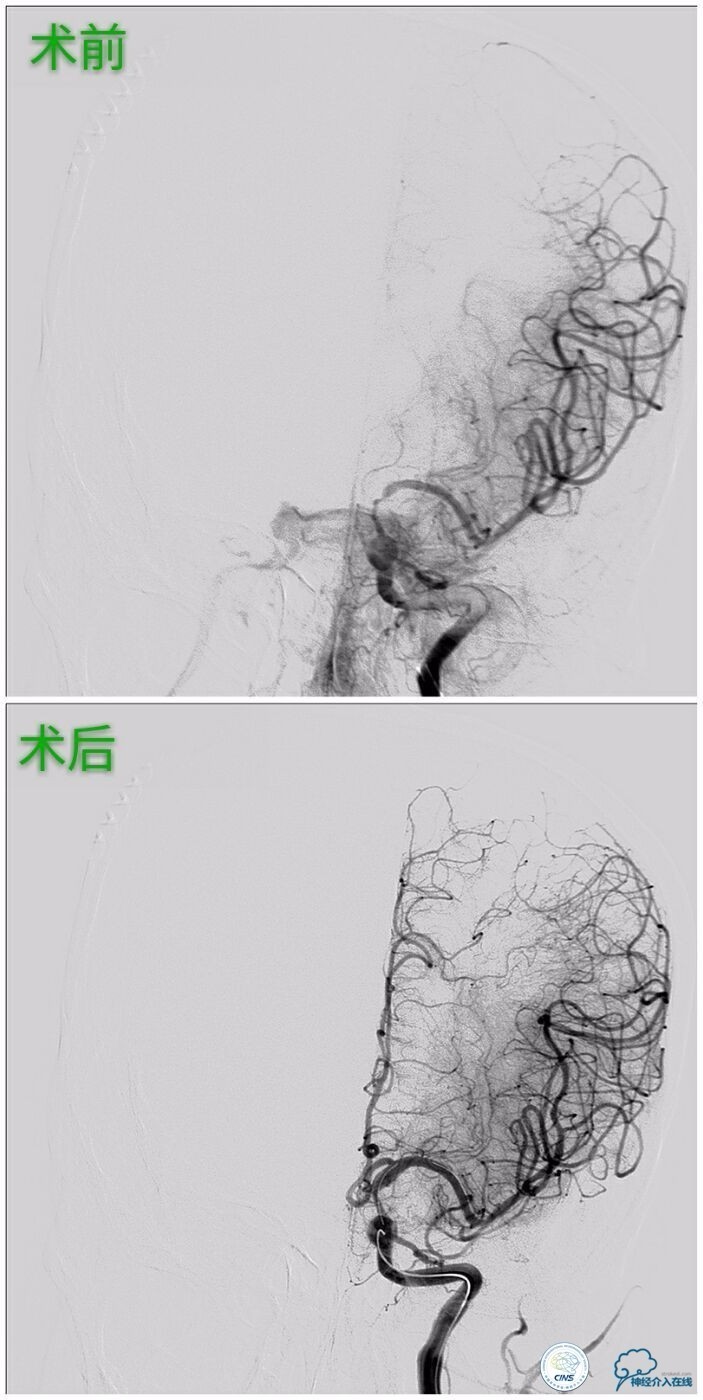

行左侧颈内交通段、左椎开口支架成形术治疗。

》左侧颈内交通段球囊扩张支架成形术:

》左侧椎动脉开口球囊扩张支架成形术: